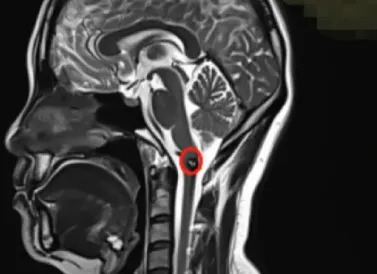

“急性血管团,确诊延髓海绵状血管瘤。”

医生气笑了,对着片子一通比划:片子上这么明显一个东西,怎么可能弄错?

医生变得非常严肃:这个位置,手术可能会偏瘫、面瘫,最坏的就是生命危险,就是在手术台上可能会有呼吸终止、心跳终止等情况,建议保守观察。